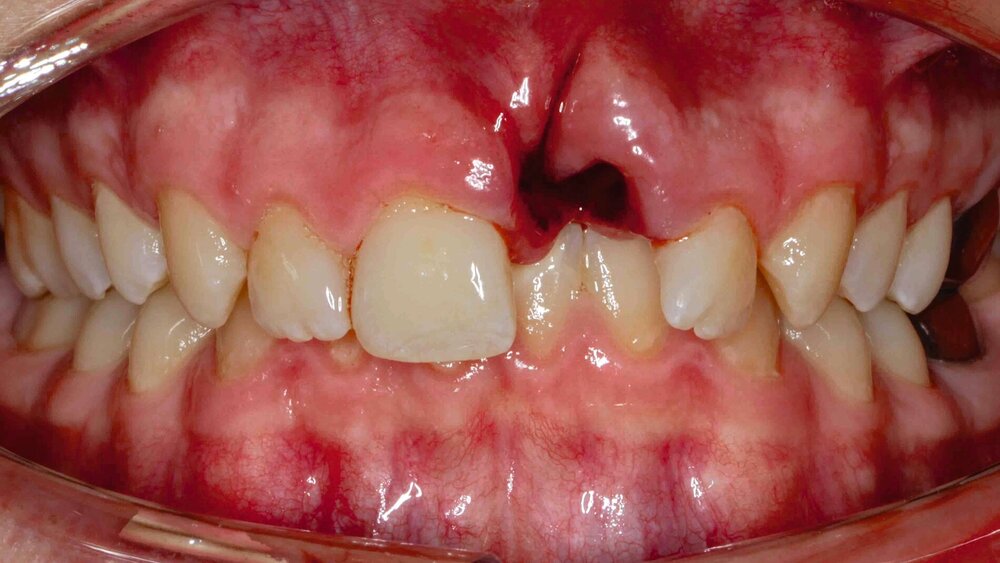

Zahnunfälle im Fokus

Die Deutsche Gesellschaft für Mund-, Kiefer- und Gesichtschirurgie e.V. (DGMKG) trat Anfang Juni in einer Pressekonferenz mit der Forderung an die Öffentlichkeit, die Zahnrettungsbox der Standardausrüstung von Rettungswagen hinzuzufügen. Rettungswagen in Deutschland seien „zwar in der Regel mit Amputatbeuteln ausgestattet, nicht aber mit Zahnrettungsboxen, was ein Mangel ist“, erklärte Prof. Dr. Dr. Hendrik Terheyden, Pressesprecher der DGMKG. Neben Schulen und Sportstätten sollten künftig auch Rettungswagen standardmäßig mit den nur wenige Euro teuren Zahnrettungsboxen ausgestattet sein, verlangt die Fachgesellschaft. Das könne mögliche Folgeschäden des Zahntraumas niedrig halten.

Entscheidend für eine gute Prognose bei avulsierten Zähnen ist die Vitalerhaltung der desmodontalen Zellen auf der Wurzeloberfläche. Das kann durch die möglichst umgehende Einlagerung des Zahnes in Zahnrettungsboxen erreicht werden. Das in den Zahnrettungsboxen enthaltene Zellkulturmedium ermöglicht den Erhalt der Vitalität der desmodontalen Zellen über etwa 24 Stunden. Als Mittel der zweiten Wahl empfiehlt die DGMKG kalte H-Milch, die der aktuellen Leitlinie zufolge für die Aufbewahrung „über wenige Stunden geeignet erscheint“.

Der Umfrage zufolge passieren die meisten Unfälle im Haushalt, wo sich 49 Prozent der Befragten ihre Verletzung zugezogen haben. Darauf folgen Sportunfälle mit 33 Prozent und Gründe wie instabile Zähne mit 18 Prozent. Körperliche Auseinandersetzungen oder Schlägereien sind mit sechs Prozent ursächlich.